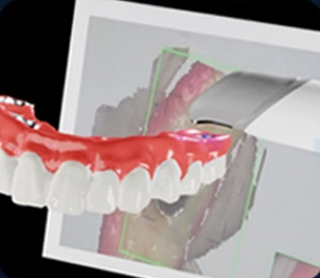

3D 컴퓨터 모의시술 및

보철물 디자인 -

유도 가이드 제작 -

진단부터 시술까지 디지털화된 데이터로 진행되어 정확하고

수준높은 치료를 쉽게 받으실 수 있습니다.